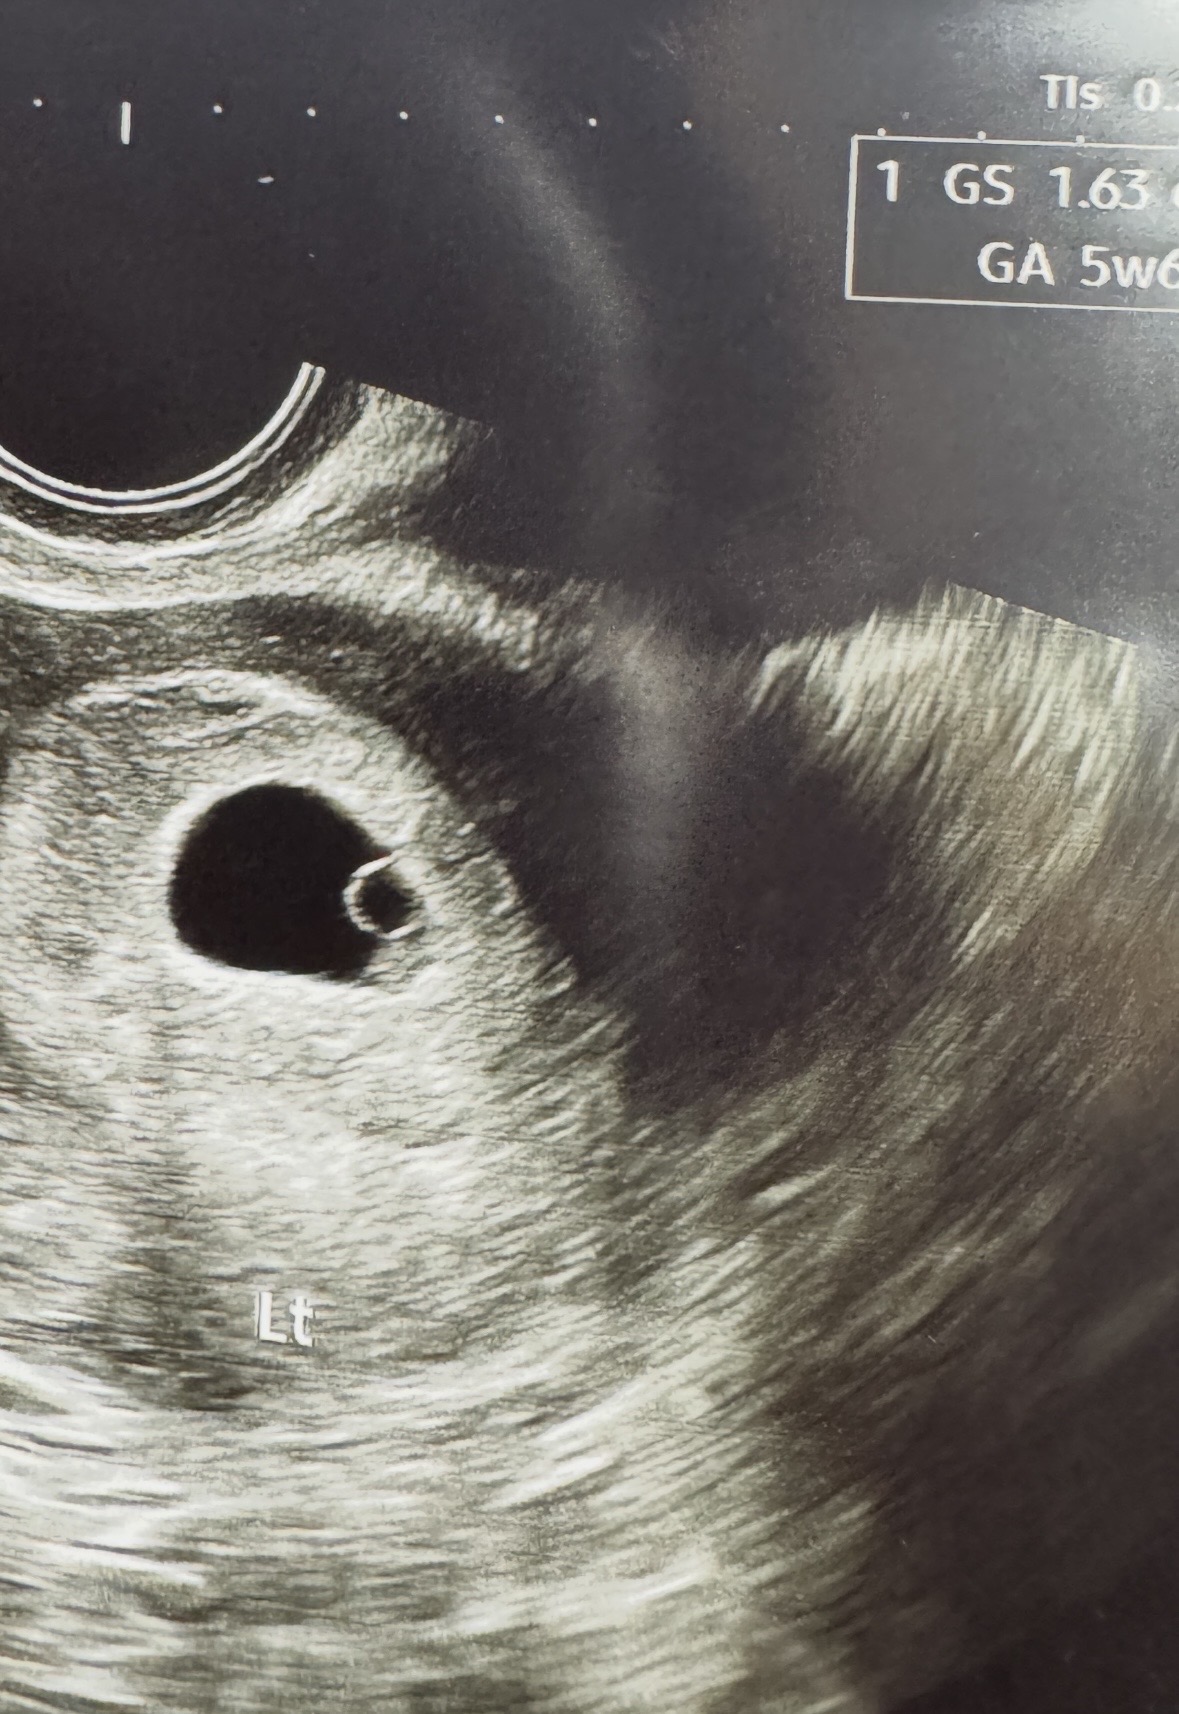

오늘로 6주0일차가 되었는데 정말 연한 갈색냉과 실피 같이 쪼금 묻어 나왔어요ㅠㅠ 생리통처럼 배가 싸하게 아픈데 괜찮겠죠..??ㅠㅠ 몇일전에 애기집에 난황까지 예쁘게 자리 잡은거 확인했는데 옆에 혹이 있다고 들었어서 불안하네요ㅠㅠ 내일 여는 병원 찾아서 아침일찍 가보긴 할건데.. 이렇게 냉 나오는거 괜찮을까요..?ㅜㅜㅠ 지금은 또 안나오는거같긴 합니다.!!!